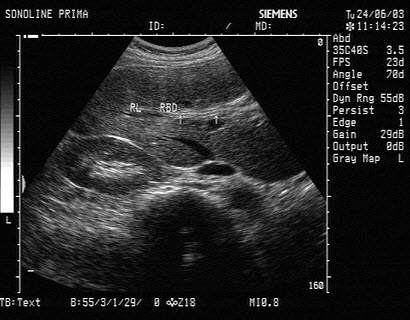

16、单项选择题

男,63岁,因左侧腰部疼痛不适伴无痛血尿1月余就诊,B超显示左肾集合系统分离3.9cm,如图所示,最可能的诊断为()

A.左输尿管结石